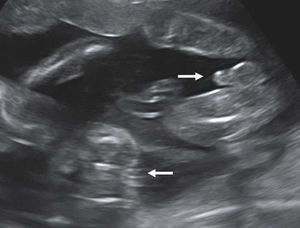

Fetal gender The identification of discordant fetal gender indicates dichorionic twinning (Fig. 6). The positive predictive value of discordant gender (when correctly identified) is 100%. However, considering that around 50% of concordant sex twins are dichorionic, the definition of chorionicity needs further sonographic signs.

Number of the placental masses The location of the placental masses has a limited value in the assessment of chorionicity. Separate placental sites are an indicator of dichorionic twins (Fig. 7). However widely separated placentas are found in only one-third of all twin gestations. Furthermore two separated placental masses may be seen in the rare cases of a monochorionic placenta which is bilobed or has a succenturiate lobe. For this reason the sensitivity of two placental sites is 32% and the PPV is 97.7%.20 A single placental mass may be indication of both monochorionic and dichorionic twins with fused placentas (Fig. 8).